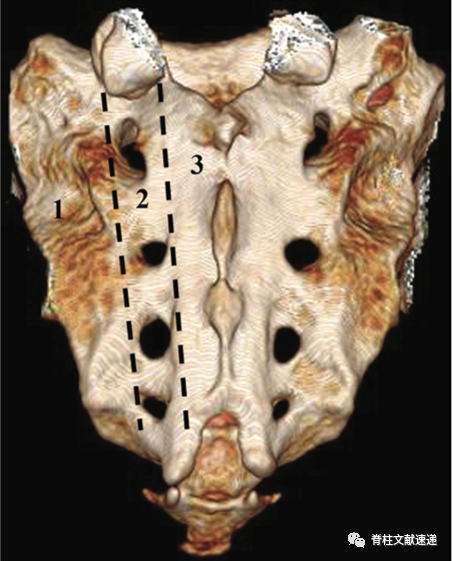

早期研究报道的骶骨衰竭骨折的发生率为1-1.8%,近期的一项研究调查了250 名到急诊科就诊并CT成像的疑似骨盆损伤患者。在被诊断患有骨盆骨折的 46 名患者中,11 名患者 (4.4%) 被发现患有骶骨衰竭骨折。多见于平均年龄 70-75 岁的患者。下图中1区为骶骨衰竭骨折常见区域。